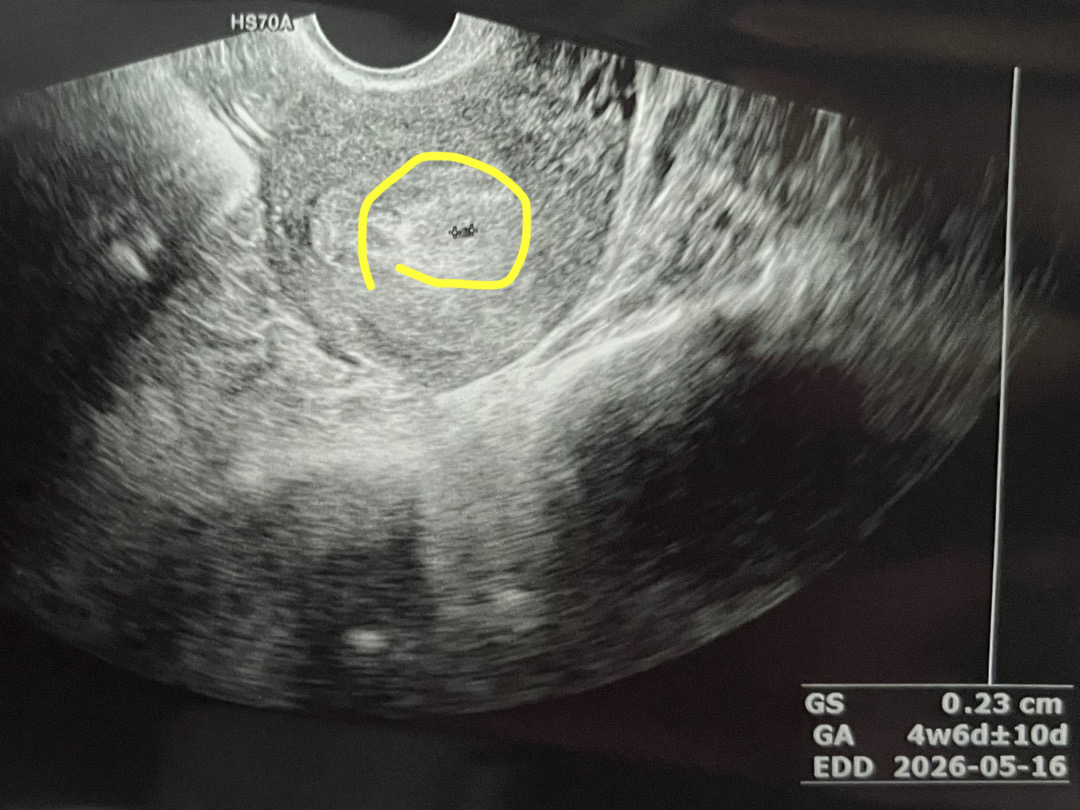

아기집 보고 왔어요(4주 6일)

네이버 기준으로는 5주 5일인데 초음파상으로는 4주 6일 나오네요! 배란이나 착상이 늦어졌나봐요~ 5주가 아직 안 됐지만 아주 작은 아기집을 보고 와서 너무 귀여웠어요 ㅎㅎ 이제 2주에 한 번씩 병원에 가면 될까요?! 6주 6일 또는 7주 쯤에 가면 난황도 보고 심장소리도 들을 수 있겠죠~?